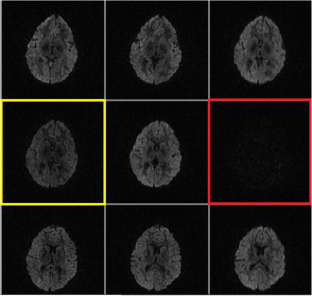

Fig. 1

Fig. 2

Fig. 3

Fig. 4

Fig. 5

Fig. 6

Fig. 7

Fig. 8